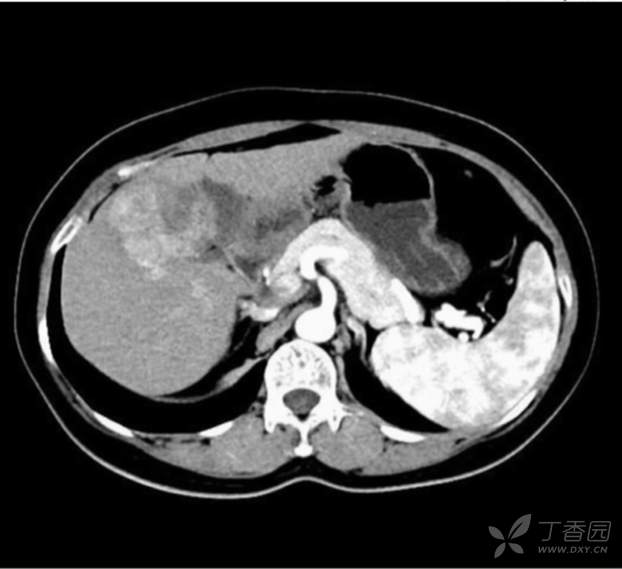

腹部 CT 提示:肝 S58 段肿块,合并出血、坏死,考虑 HCC 可能性大;肝中静脉,胆囊底部受侵犯可能,肝多发再生结节;肝硬化;脾大。

CT 动脉期